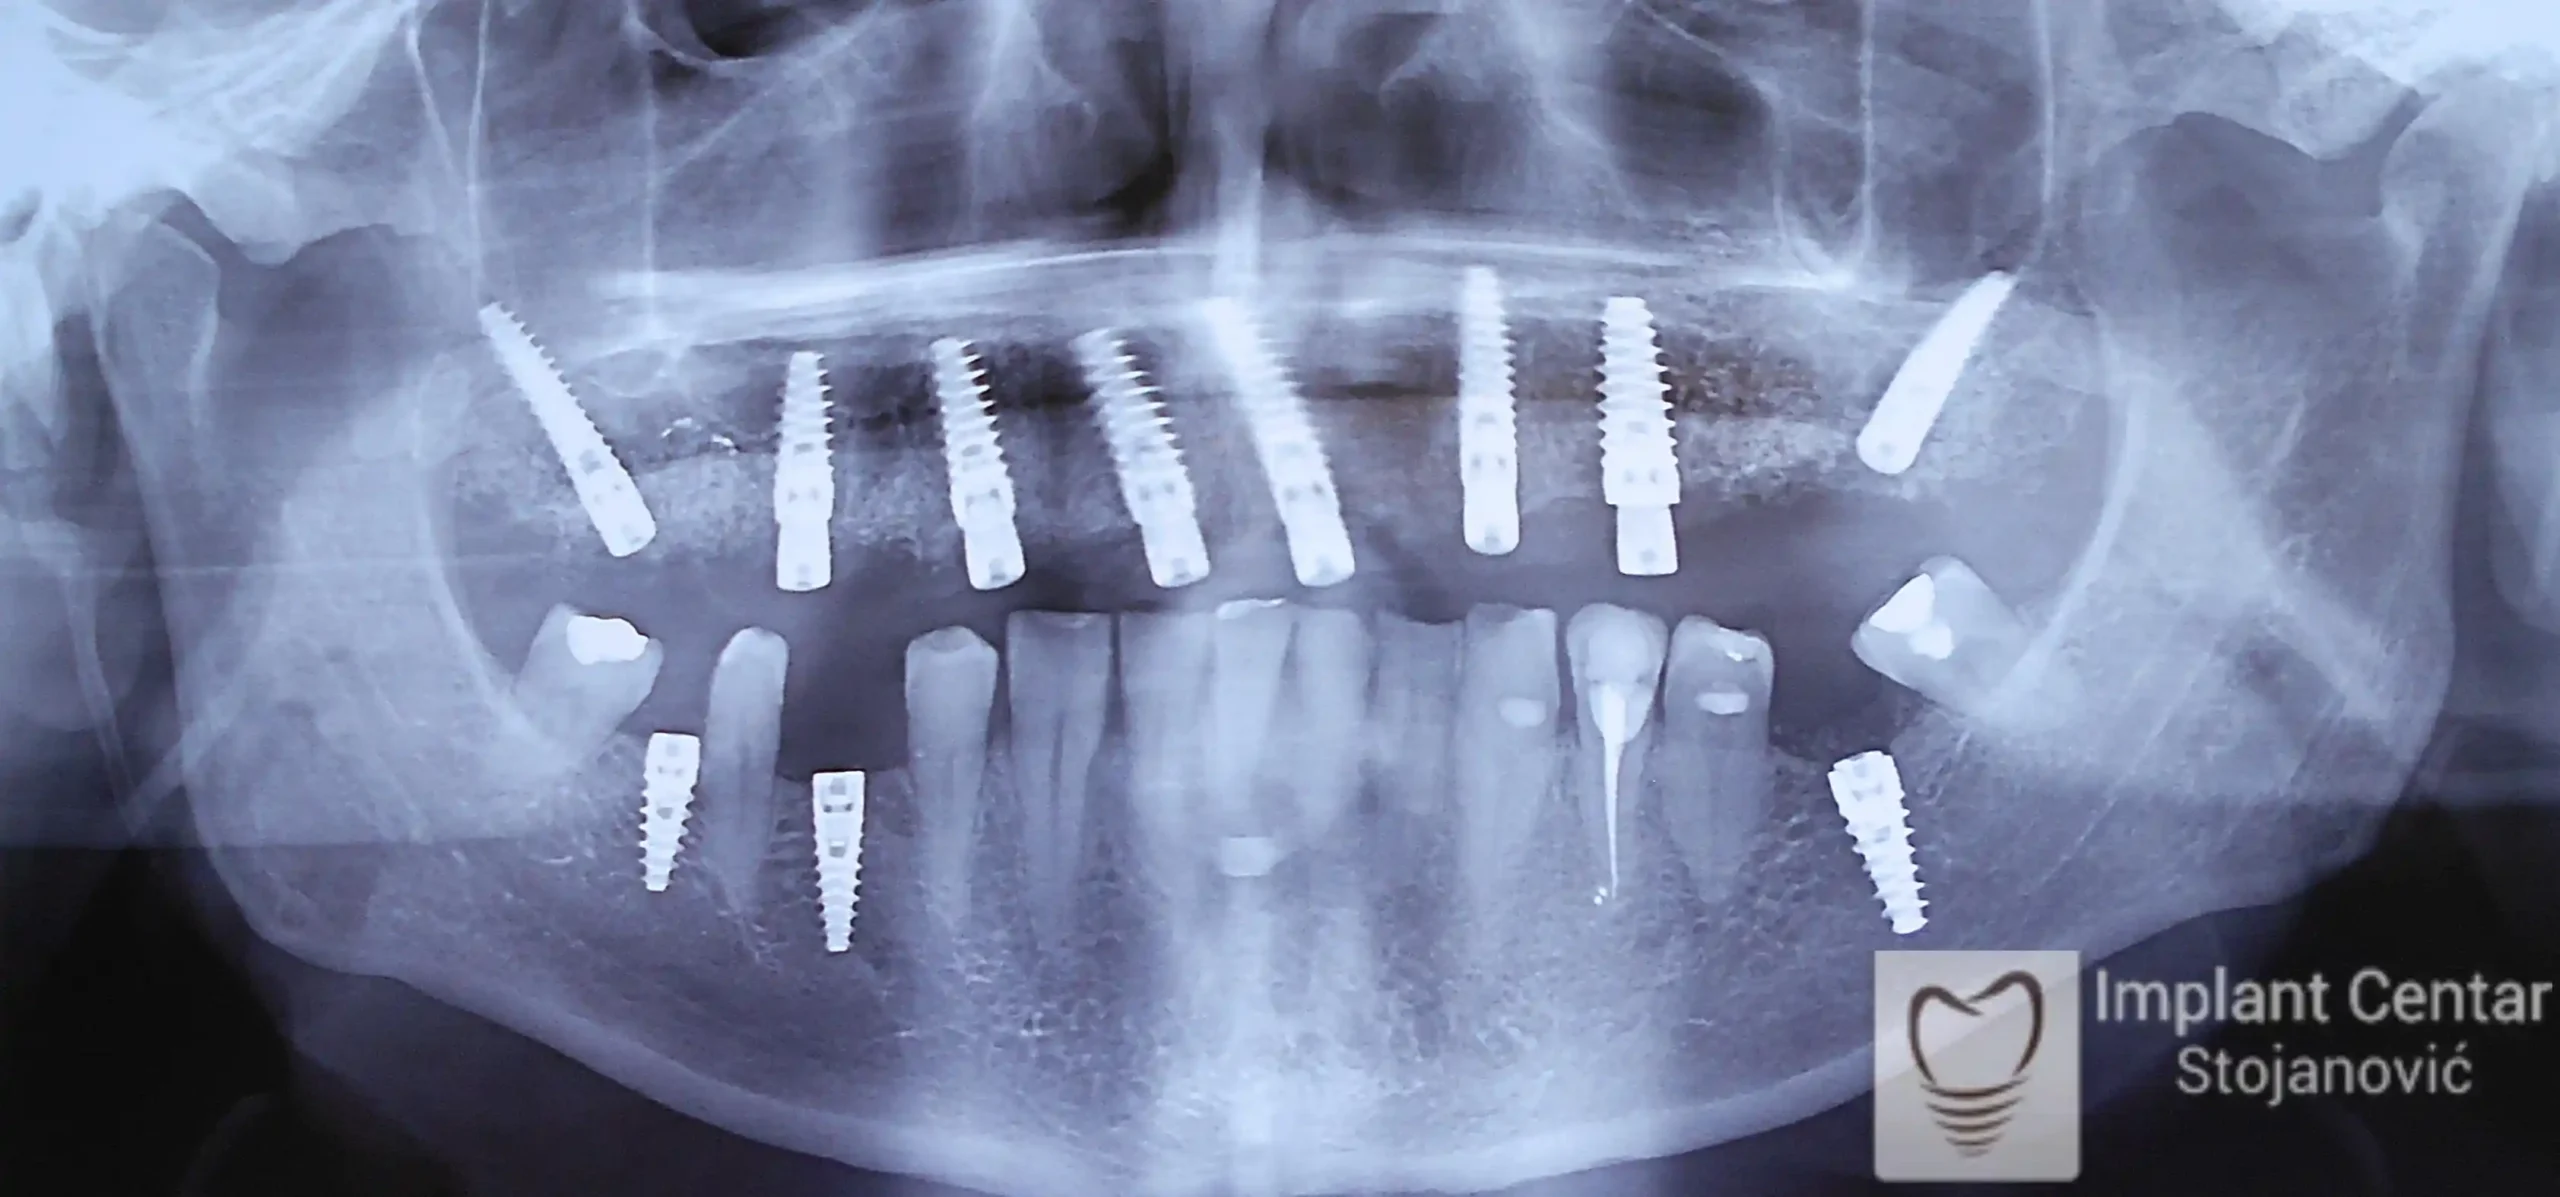

Na slici 1. slici 2. vidi se početno stanje — pacijent je imao prirodne zube, ali samo izradom novih mostova nije bilo moguće postići normalan odnos gornjih i donjih zuba (eugnatan zagrižaj).

Zbog toga je plan terapije uključivao vađenje svih preostalih zuba i ugradnju implantata u gornjoj i donjoj vilici. U gornjoj vilici postavljena su i dva tuberopterigoidna implantata, kao zamena za sinus lift proceduru, što se može videti na ortopan snimku nurađenom odmah nakon ugradnje (slika 3).

Već tri dana nakon operacije, pacijent je zbrinut fiksnim privremenim zubima na implantatima, čime je odmah povraćena funkcija i estetika osmeha.

Nakon završetka perioda integracije implantata, izrađeni su cirkonijum-keramički mostovi u gornjoj i donjoj vilici (slika 6.).